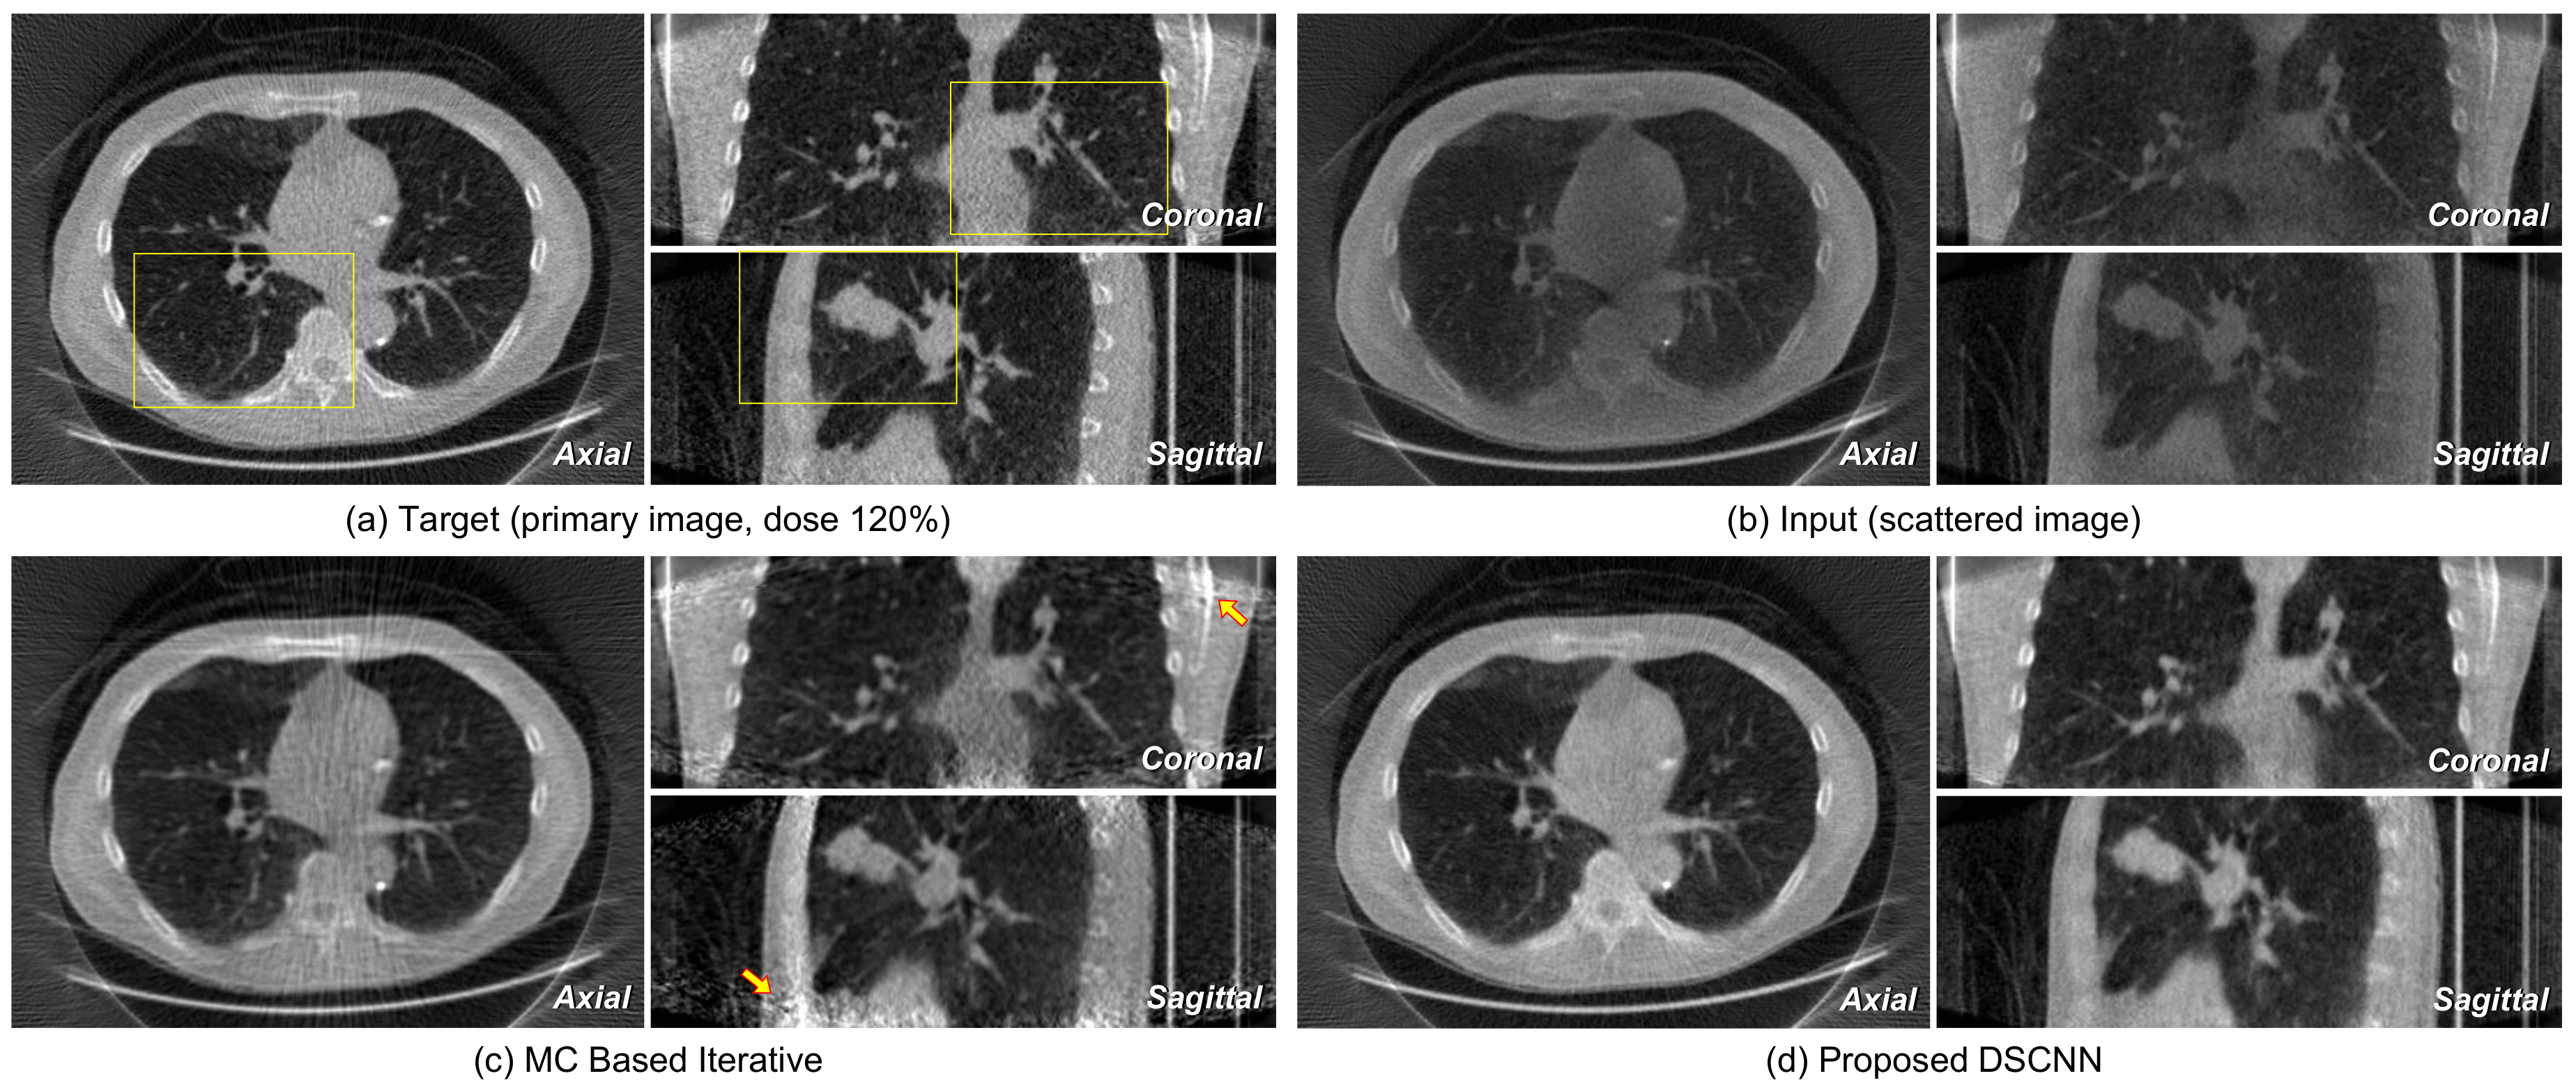

Figure 11 shows the axial images taken from reconstructed volumes with specific profile data. The superiority of the proposed DSCNN against MC-based method is evident from both the sliced image and the profile. Figure 12a,b represents the axial, coronal, and sagittal images of a target and its corresponding input scattered image, respectively. Figure 12c shows that no additional artifact is generated from the proposed DSCNN, as opposed to the MC-based iteration method in Figure 12d. However, additional artifacts are seen in the coronal and sagittal images at the arrow-indicted parts of the images from the MC-based iteration method. The regions enclosed by the yellow rectangles in Figure 12 are magnified in Figure 13. The proposed DSCNN enhances the bone boundary in the axial image (arrow), recovers the morphological information in the coronal image (circle), and well reveals the shading in soft structure in the sagittal image (arrow). The MC-based iterative method produces additional noise in the soft structure.